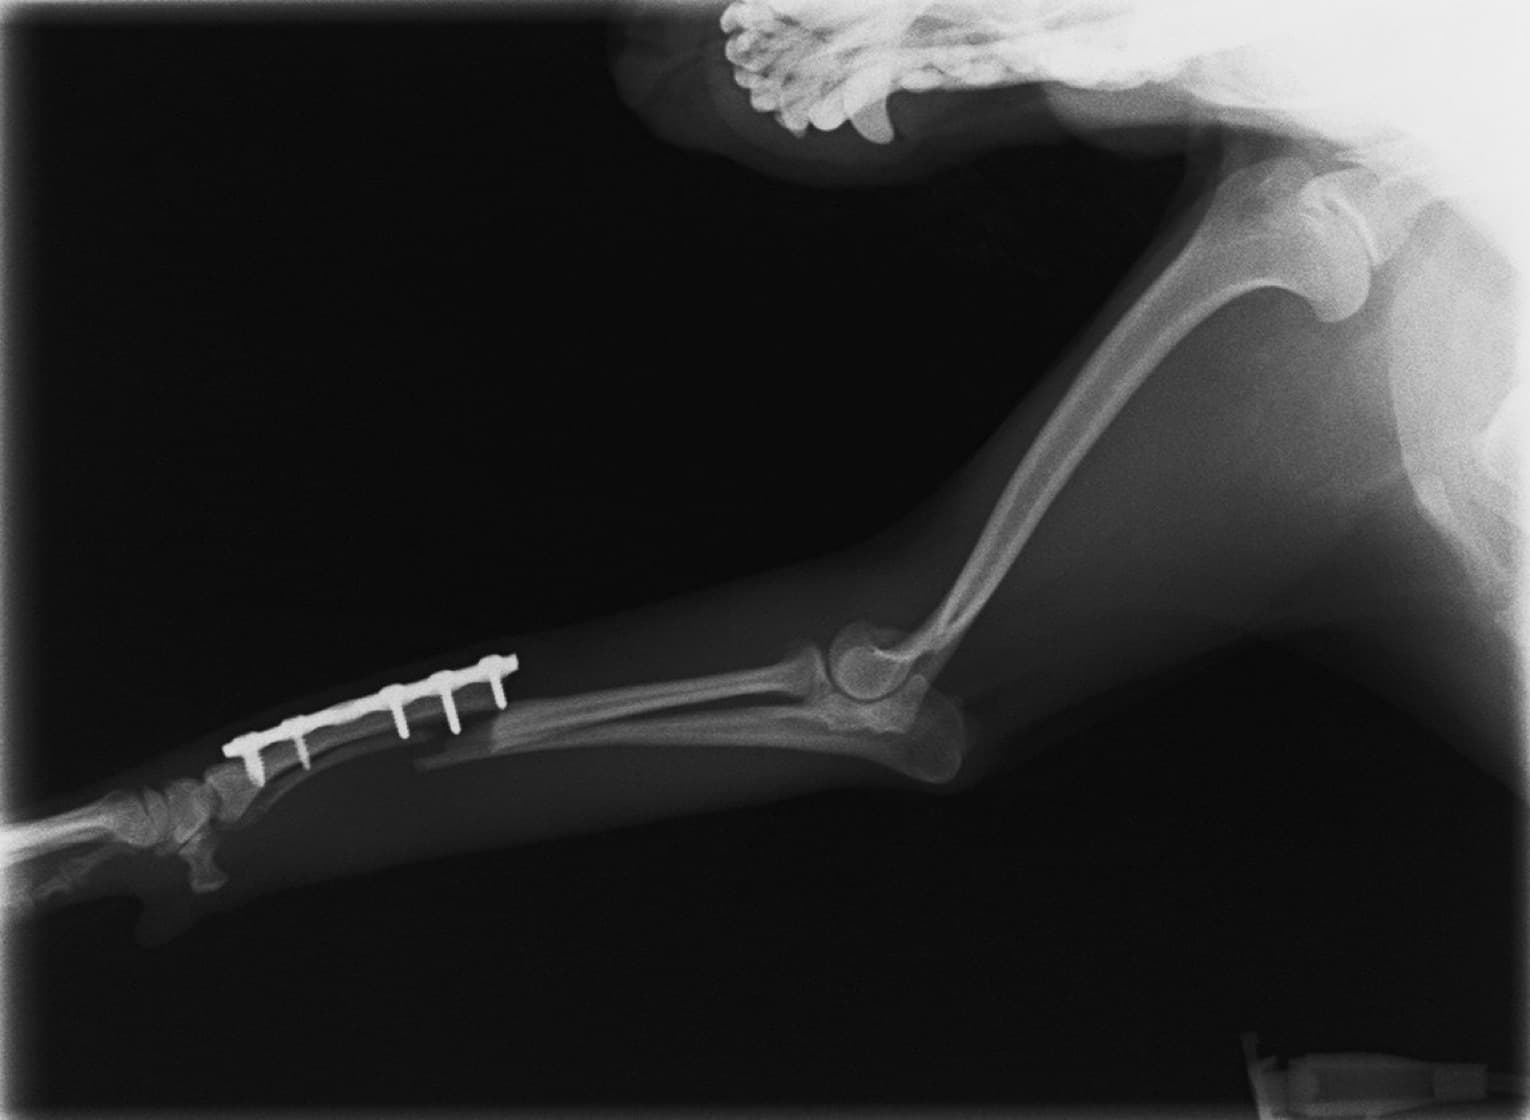

トイプードル 右遠位橈尺骨短斜骨折のALPSによる内固定

当院ではAdvanced Locking plate system(ALPS)と、Locking compression plate system(LCPS)という骨接合法で骨折症例の治療を行っています。

従来型のプレートのように広い面積で骨と接するプレートを用いて固定を行った場合、プレート下の骨はプレートとの接触面において血行が絶たれ壊死し、それがリモデリングされると骨密度が低下する。この骨密度の低下防ぐために、骨折部局所への血行を温存することの重要性が近年改めて認識されるようになってきている。Advaed Locking Plate System (ALPS)は従来型のプレートシステムの欠点を改良し、より使いやすく、より骨への血行を阻害しないようにというコンセプトで作られた。

LCPは、スクリュー(ネジ)とプレート(金属の板)をロックする特殊な構造により骨折部位を固定する新しい世代のプレートシステムです。ひとつのホールでロッキングスクリューとスタンダードスクリューの使用を選択できるユニークな構造をしているため、骨折断端間の圧迫を目的とした従来型プレート固定法に加え、高い角度安定性を有するロッキングスクリューを用いた固定法の選択が可能です。従来のプレートシステムでは困難だった部分の骨折や癒合不全の症例に高い治療効果をもたらします。